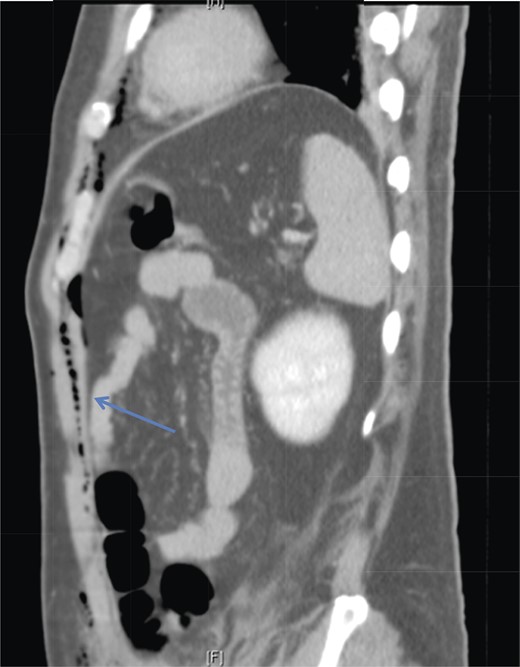

Sagittal section of CT abdomen demonstrates air tracking along the anterior extraperitoneal space (arrowhead) into the anterior mediastinum and preperitoneal fat.

Laparoscopic CO2 can enter the retroperitoneal space and track along tissue planes into the pleural space and mediastinum [4]. Chien and Soifer [7] reported a case of pharyngeal emphysema complicating a laparoscopic hernia repair, and postulated that myopectineal dissection may lead to CO2 tracking retroperitoneally into the thorax. This is a possible cause of pneumomediastinum in our patient, as his CT imaging showed the presence of left posterior pararenal stranding, supporting a possible retroperitoneal dissection of CO2 to the thoracic cavity. Another pathway for transdiaphragmatic extension of air into the mediastinal space was proposed by Meyers [8]. The endothoracic fascia is continuous with the extraperitoneal space of the fascia transversalis. Extraperitoneal gas can dissect through the anterior gaps of the diaphragm between the sternal, xiphoid and costal origins of the diaphragm. With the aid of anatomical studies in cadavers, Kleinman et al. confirmed these observations [6]. This potential pathway likely explains the entry of CO2 from our patient's abdominal wall (extraperitoneal space) into the mediastinum, without the presence of pneumoperitoneum.